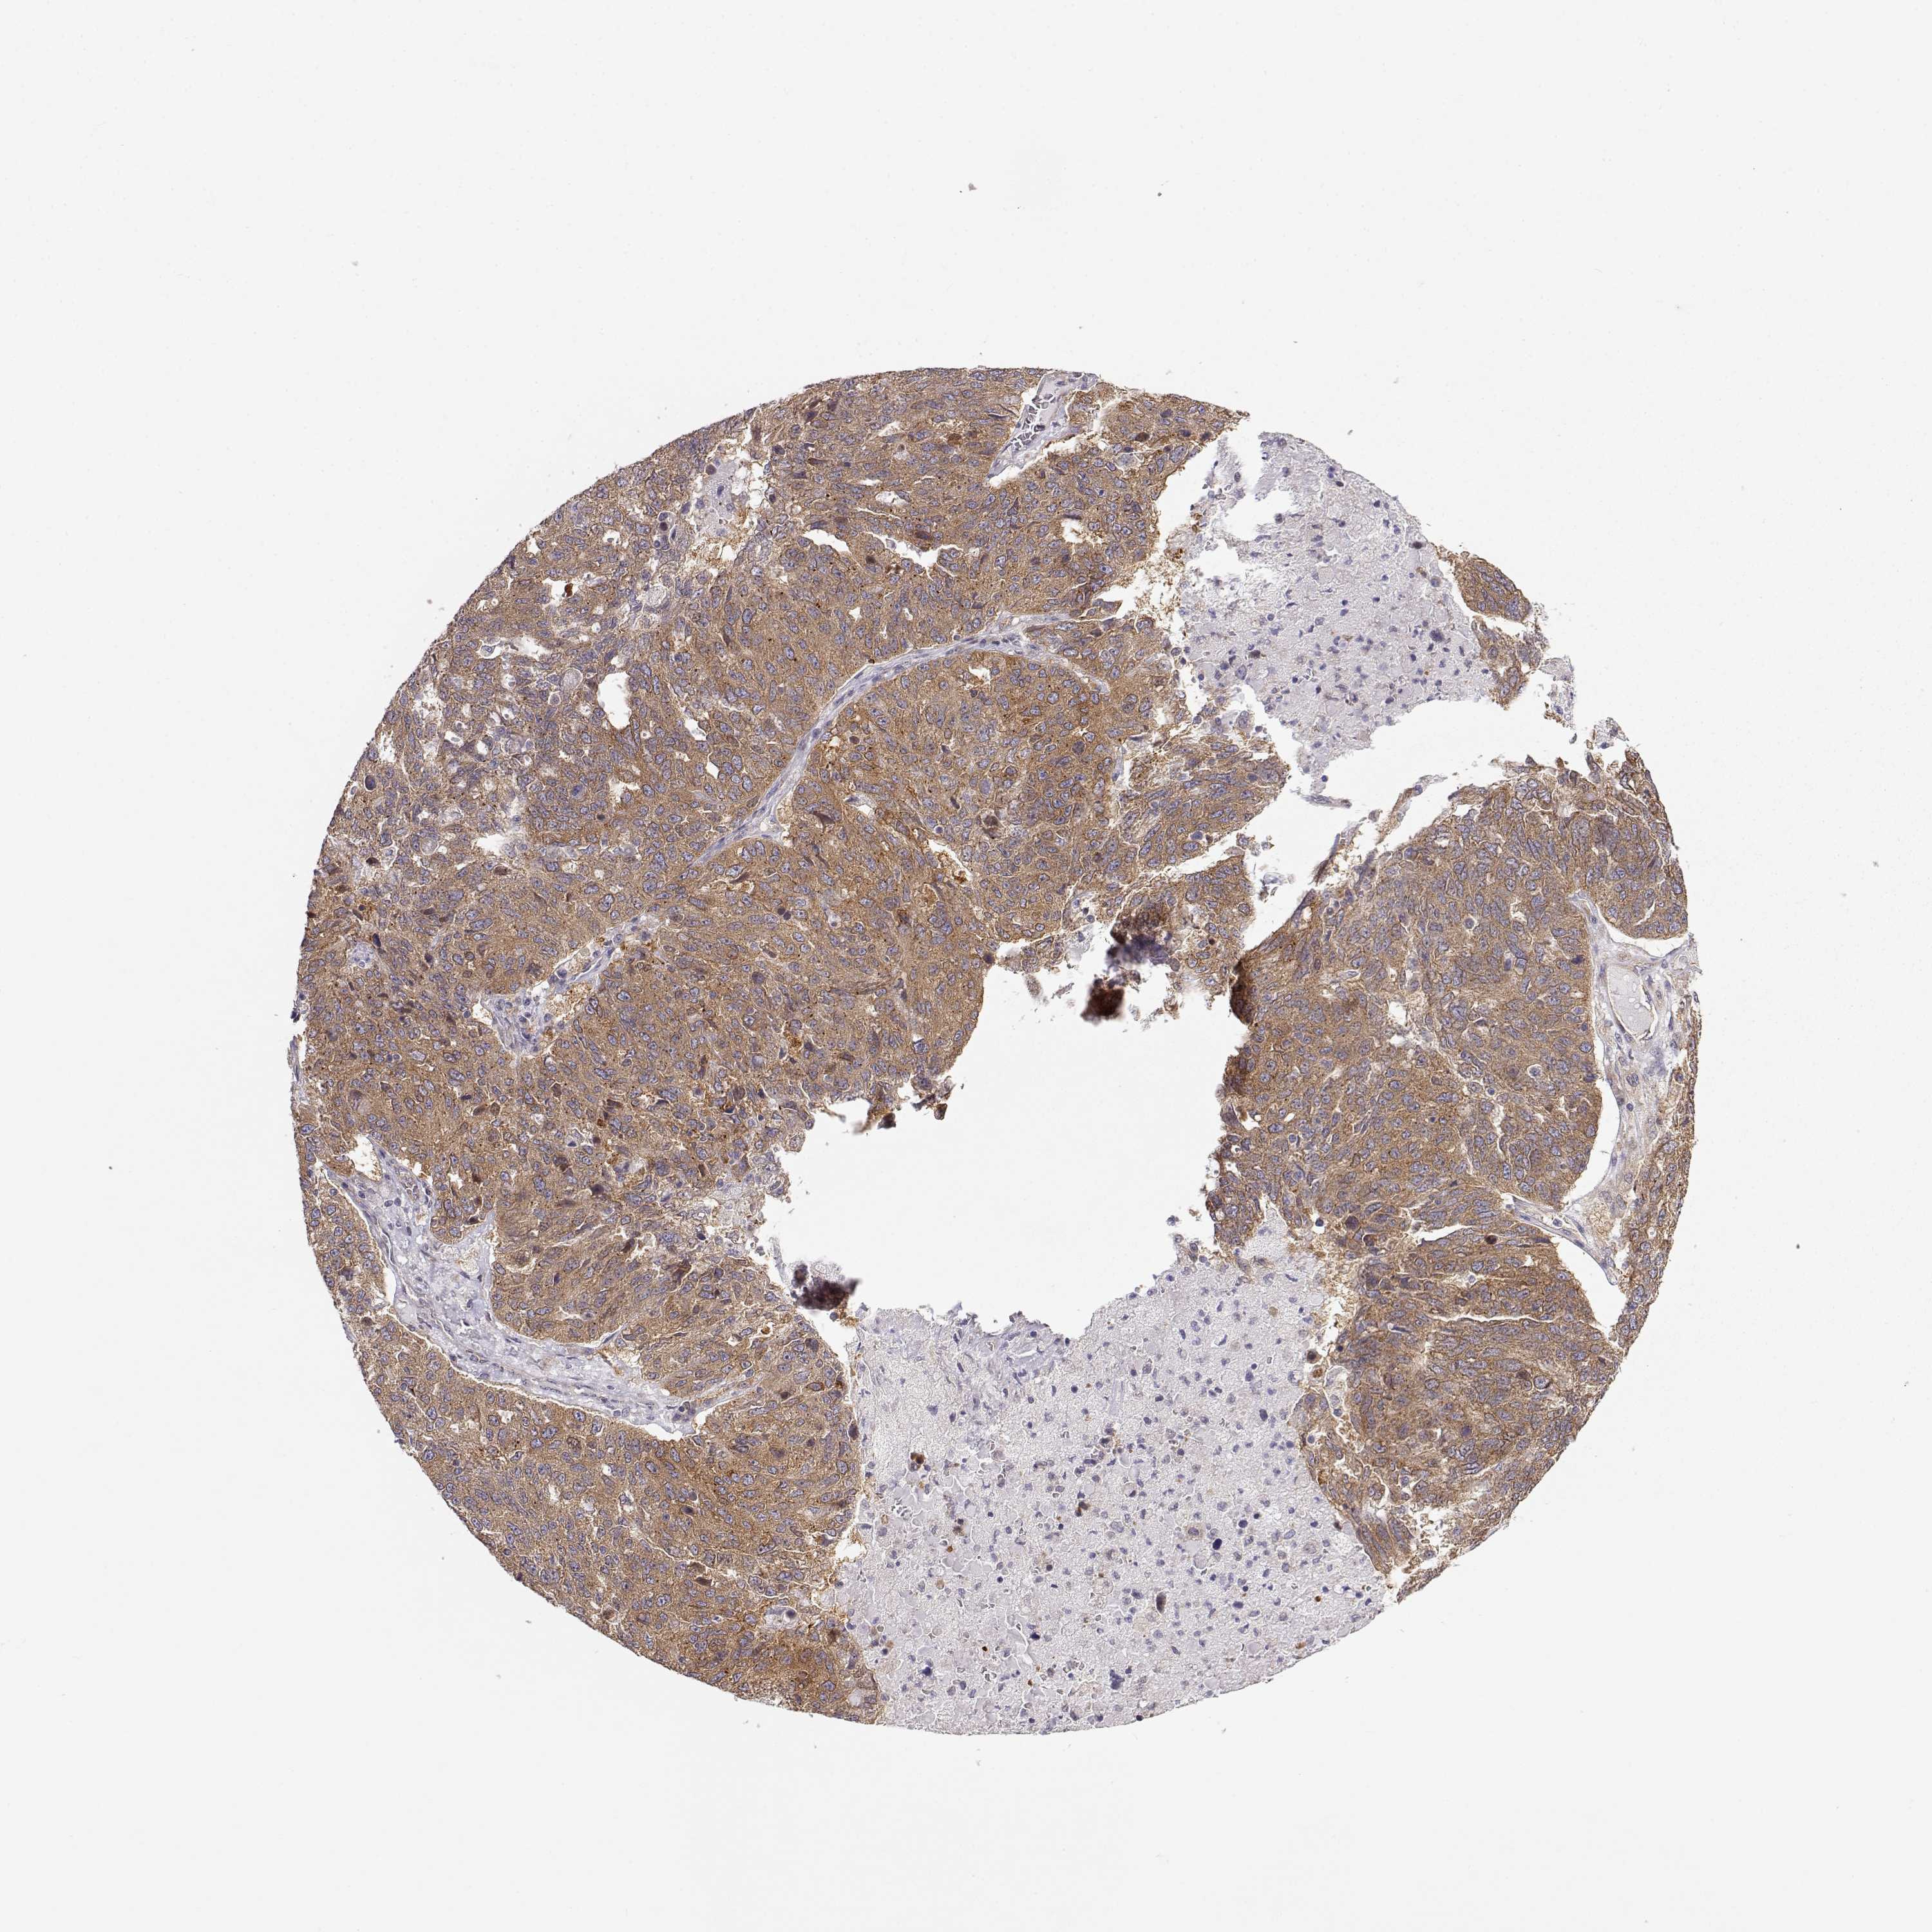

OVARIAN CANCER - Protein expressioni

A mouse-over function shows sample information and annotation data. Click on an image to view it in a full screen mode. Samples can be filtered based on level of antibody staining by selecting one or several of the following categories: high, medium, low and not detected. The assay and annotation is described here.

Note that samples used for immunohistochemistry by the Human Protein Atlas do not correspond to samples in the TCGA dataset.

Antibody stainingi

Antibody staining in the annotated cell types in the current human tissue is reported as not detected, low, medium, or high, based on conventional immunohistochemistry profiling in selected tissues. This score is based on the combination of the staining intensity and fraction of stained cells.

Each image is clickable and will lead to virtual microscopy that enables deeper exploration of all samples and also displays staining intensity scores, fraction scores and subcellular localization as well as patient and tissue information for each sample.

Antibody HPA073653

Cystadenocarcinoma, serous, NOS

Cystadenocarcinoma, mucinous, NOS

Carcinoma, endometroid